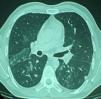

La exploración física fue normal, y la analítica general no mostraba hallazgos relevantes. El estudio de función pulmonar mostró una capacidad vital forzada (FVC) de 4,94 l (91%), un volumen espiratorio forzado en el primer segundo (FEV1) de 3,96 l (93%), un cociente FEV1/FVC del 80%, un volumen residual (RV) del 80%, una capacidad pulmonar total (TLC) del 91%, un test de transferencia del monóxido de carbono (TLCOsb) del 75% y una (TLCOva) del 88%. La prueba broncodilatadora y la prueba de provocación bronquial inespecífica con metacolina fueron negativas. La tomografía computarizada (TC) de tórax mostró un patrón micronodulillar con zonas parcheadas de vidrio deslustrado (fig. 1).